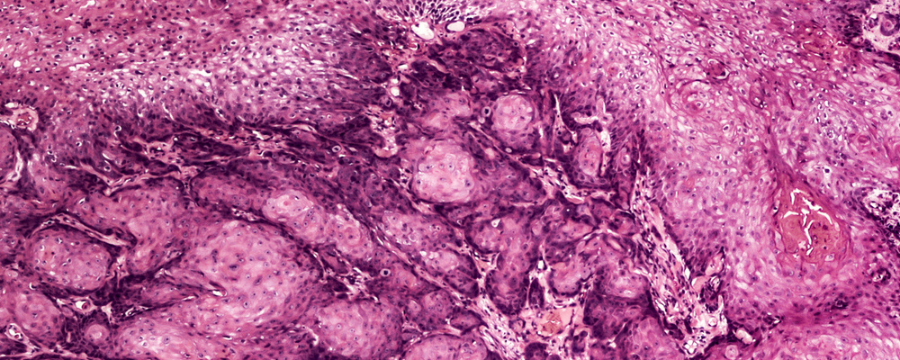

¿Qué son los condilomas acuminados?

Los condilomas acuminados son verrugas que aparecen en los genitales debido al virus del papiloma humano (VPH). Este tipo de manifestación aparece, sobre todo, con las cepas 6 y 11 del VPH, que son dos de los tipos existentes que hay de bajo riesgo. Por lo tanto, la aparición de las verrugas no deben generar preocupación sobre la posibilidad de que estas se conviertan en un cáncer o sean malignas de algún modo.